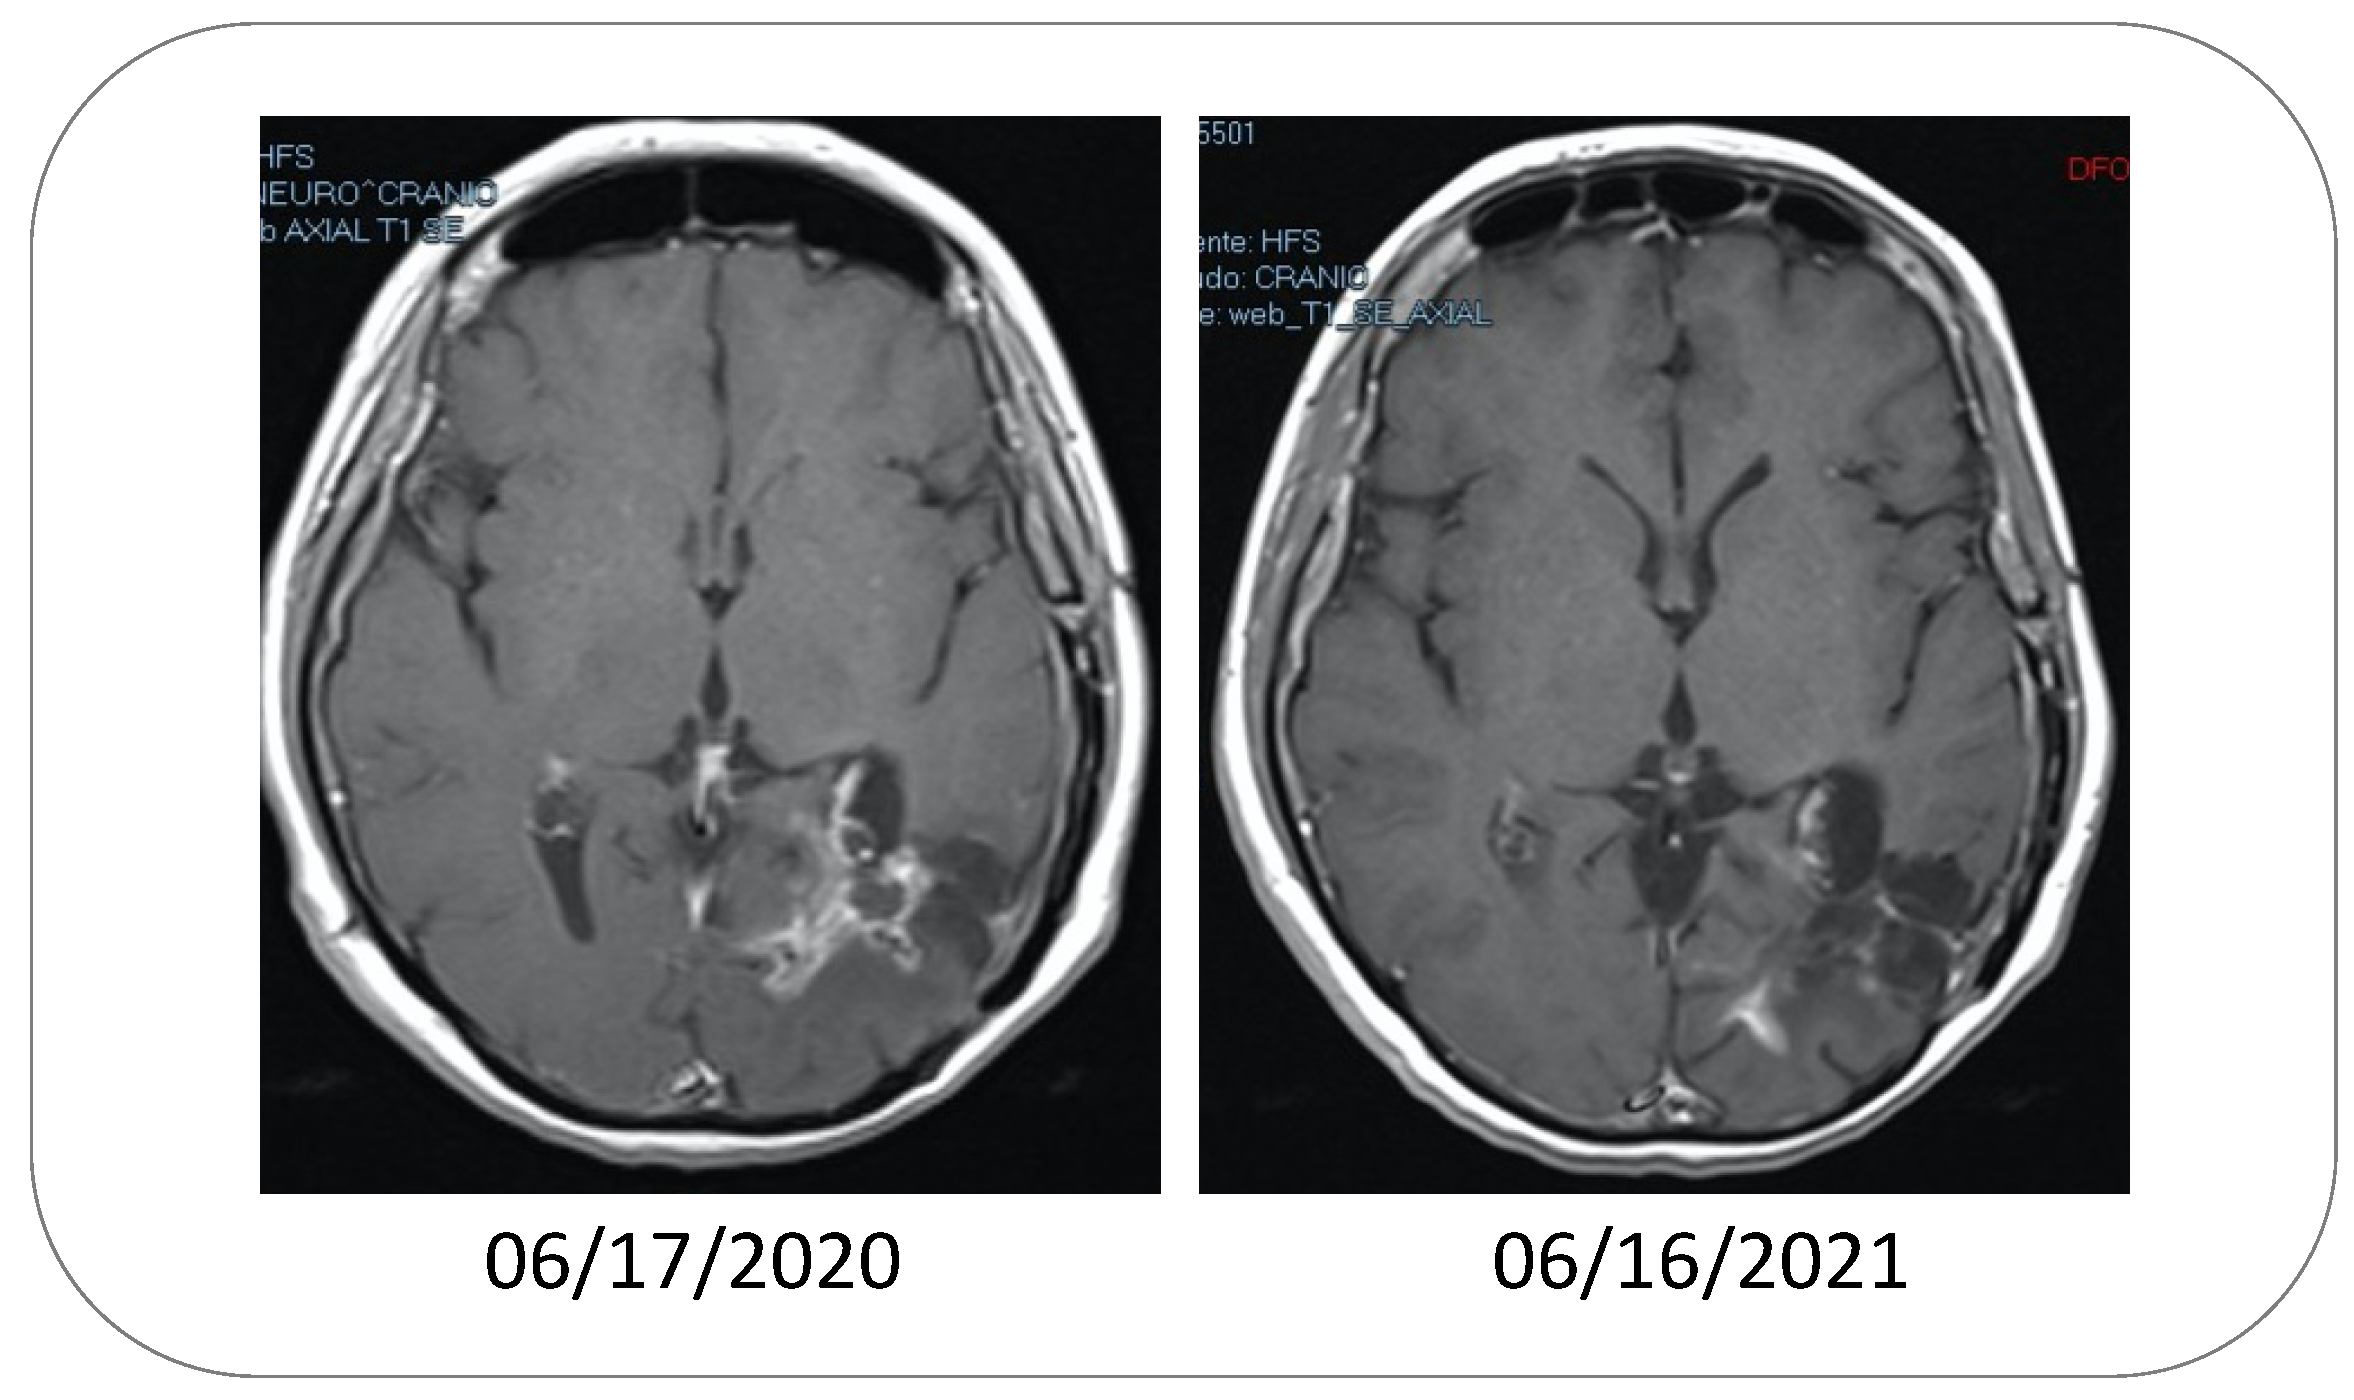

- Da Fonseca, C.O.; Simão, M.; Lins, I.R.; Caetano, R.O.; Futuro, D.; Quirico-Santos, T. Efficacy of monoterpene perillyl alcohol upon survival rate of patients with recurrent glioblastoma. J. Cancer Res. Clin. Oncol. 2010, 137, 287–293. [Google Scholar] [CrossRef] [PubMed]

- Da Fonseca, C.O.; Teixeira, R.M.; Silva, J.C.T.; Fischer, J.D.S.D.G.; Meirelles, O.C.; Landeiro, J.A.; Quirico-Santos, T. Long-term outcome in patients with recurrent malignant glioma treated with Perillyl alcohol inhalation. Anticancer Res. 2013, 33, 5625–5631. [Google Scholar]

- Da Fonseca, C.; Soares, I.P.; Clemençon, D.S.; Rochlin, S.; Cardeman, L.; Quirico-Santos, T. Perillyl alcohol inhalation concomitant with oral temozolomide halts progression of recurrent inoperable glioblastoma: A case report. J. Histol. Histopathol. 2015, 2, 12. [Google Scholar] [CrossRef]

- Santos, J.G.; Da Cruz, W.M.S.; Schönthal, A.H.; Salazar, M.D.; Fontes, C.A.P.; Quirico-Santos, T.; Da Fonseca, C.O. Efficacy of a ketogenic diet with concomitant intranasal perillyl alcohol as a novel strategy for the therapy of recurrent glioblastoma. Oncol. Lett. 2017, 15, 1263–1270. [Google Scholar] [CrossRef] [PubMed]

- Santos, J.G.; Faria, G.; Cruz, W.D.C.S.D.; Fontes, C.A.; Schönthal, A.H.; Quirico-Santos, T.; Da Fonseca, C.O. Adjuvant effect of low-carbohydrate diet on outcomes of patients with recurrent glioblastoma under intranasal perillyl alcohol therapy. Surg. Neurol. Int. 2020, 11, 389. [Google Scholar] [CrossRef] [PubMed]